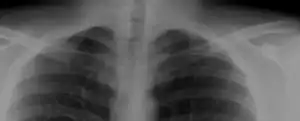

Most cases of cervical ribs are not clinically relevant and do not have symptoms;[7][8] cervical ribs are generally discovered incidentally, most often during x-rays and CT scans.[3][4][6] However, they vary widely in size and shape,[3] and in rare cases, they may cause problems such as contributing to thoracic outlet syndrome,[7] because of pressure on the nerves that may be caused by the presence of the rib.[7][9]